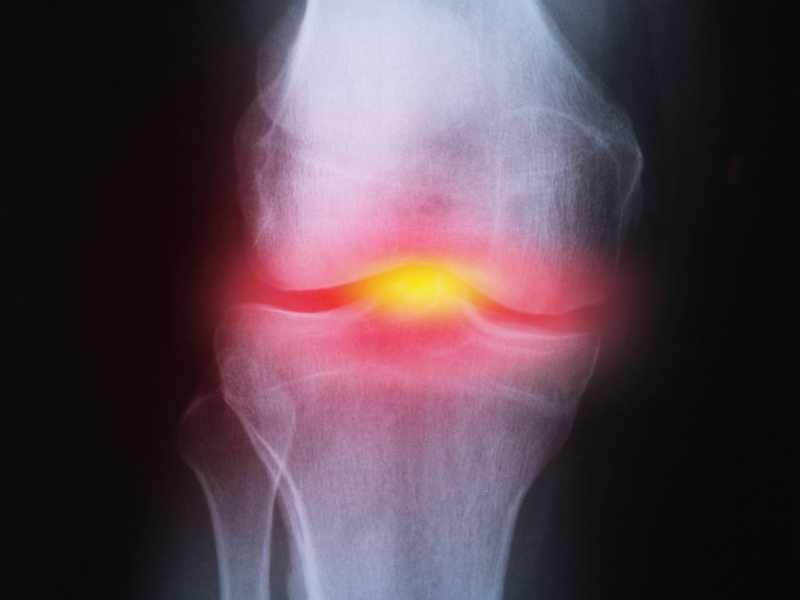

La articulación de la rodilla está compuesta por hueso, cartílago, ligamentos y líquidos, además de los músculos y los tendones, que son los que ayudan a que la rodilla se mueva en su articulación. Cualquiera de estas estructuras es susceptible de dañarse y ocasionar dolores o limitaciones en la movilidad.

Las principales causas del dolor en las rodillas suelen ser la artritis y la artrosis, trastornos que puede darse tanto en hombres como en mujeres, aunque a partir de los 55 años sea 1,5 veces más frecuente en ellas. De hecho, se estima que una de cada diez personas en España padecerá artrosis de rodilla en alguna etapa de su vida. Pero también puede deberse a lesiones o enfermedades, algunas de ellas graves.

Osteoartritis o artrosis. Es el tipo más frecuente de artritis. Cuando se da en la rodilla, provoca un deterioro del cartílago producido por el uso y la edad, generalmente.

En cualquier caso, el médico realizará un examen físico y las pruebas diagnósticas que considere oportunas para descubrir la causa, como radiografías, densitometrías, resonancias, artroscopias, biopsias, tomografías computarizadas, etc. Dependiendo del problema, se requerirá la intervención del fisioterapeuta, el traumatólogo, el médico ortopedista o el reumatólogo.